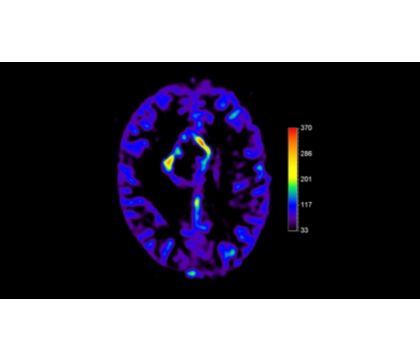

*pCASL (pseudo-Continuous Arterial Spin Labeling) ermöglicht die Darstellung der zerebralen Perfusion und funktionellen Physiologie auf kontrastfreie Weise mit geringer Verzerrung* und unter Abdeckung des gesamten Gehirns.